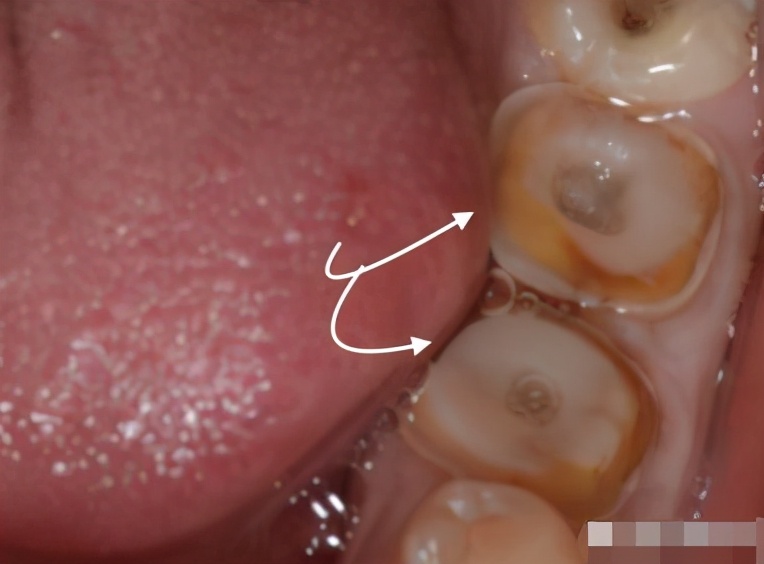

1、基牙腐烂

很多人认为只要套上牙冠,牙齿就“刀枪不入”了!实际上,就算套上牙冠,也极有可能发生蛀牙,戴牙冠发生蛀牙的常见部位通常在牙冠和牙齿龈线边的接合处。

如果出现这种情况,则需要及时去检查看是否需要更换新牙冠。